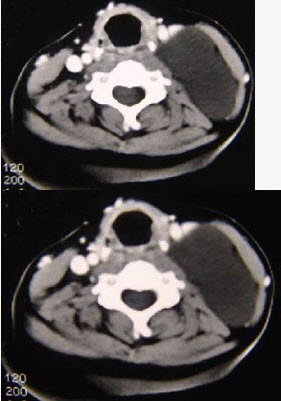

男性,40岁,颈部出现无痛性囊性包块2年余,CT扫描如图所示,最可能诊断为()。

A、淋巴管瘤

B、血管瘤

C、淋巴结肿大

D、神经源性肿瘤

E、颈动脉鞘瘤

A